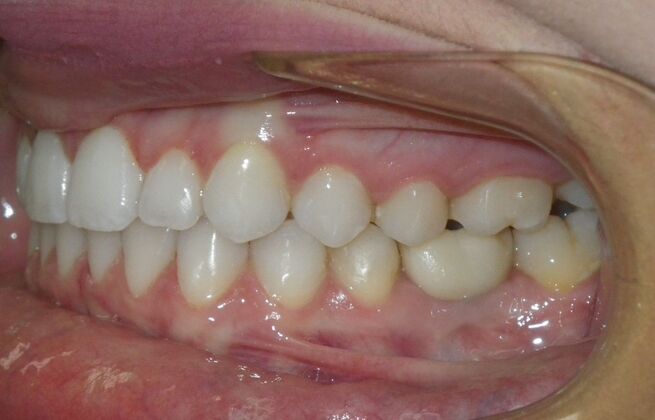

This patient was an awesome dental assistant for our practice and we were all very sad when she had to move closer to her home. She was very interested in correcting some minor spacing and rotations in her upper and lower anterior teeth and to decrease her overbite as well.Treatment took about 12 months, but we were pleased with the results and fabricated clear invisalign vivera retainers. We are still hoping one day she will return to be with us again.